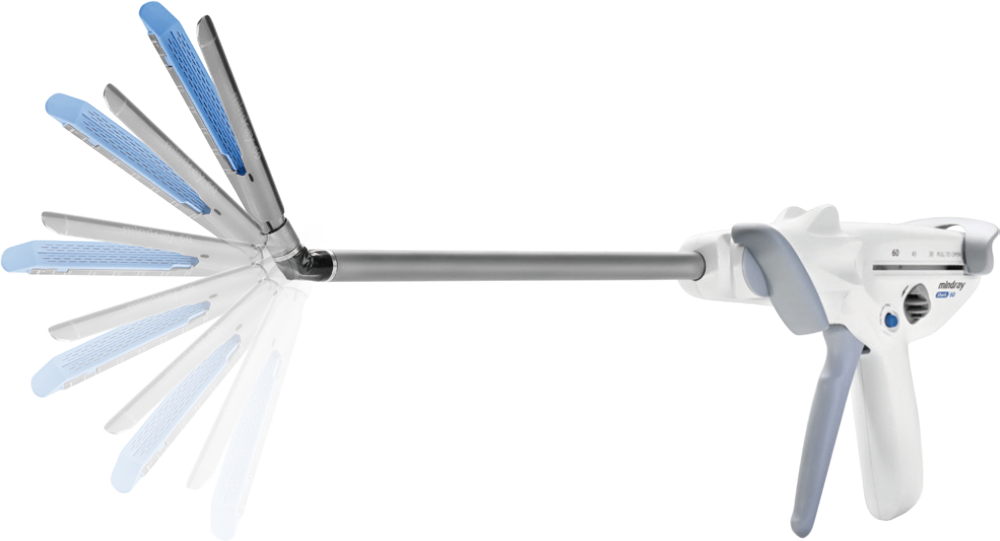

Resilient and Flexible, Easy to Operate

Innovative and thoughtful design for different surgical procedures, making operation easier and more efficient.

Detachable Curved Anvil Tip for Versatile Use

Single -step installation and removal designed for superior efficiency and convenience; Enables easy insertion through the hole in complex tubing structures, suitable for diverse applications, including cutting and stapling blood vessels and tissues.

60┬░ Articulating Angle,

Providing Exceptional Flexibility

In narrow anatomical cavities such as the lower anterior rectum, left upper lung, and gastroesophageal junction, 60┬░arti culation allows for precise placement and dissection.